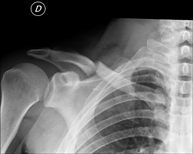

- Osteoarticular

- RX Extremitats

Tècnica que usa els raigs X a través de la qual s'obtenen imatges de l'interior de les extremitats per al seu estudi, especialment dels ossos. Indicacions: traumatisme, infeccions articulars. - RX Artrografia